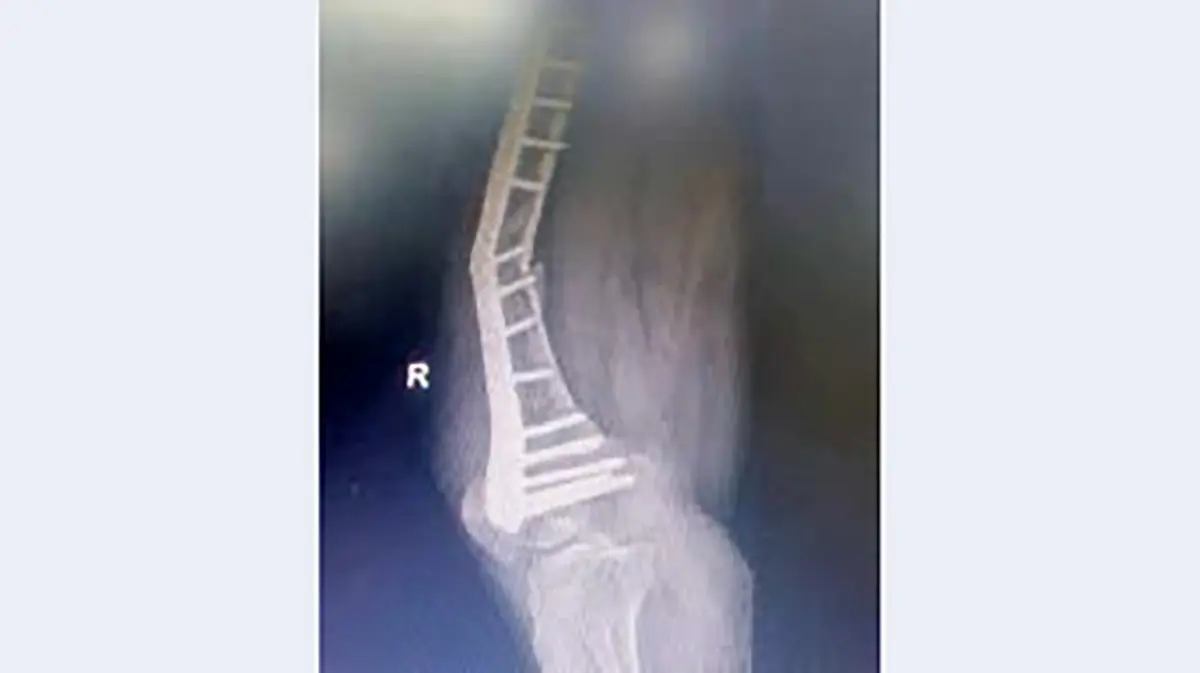

حوادث رکنا : دوم شهریور گزارشی با عنوان «جنجال پلاتین های مشکوک» منتشر شد که بیانگر کج شدن پلاتین های بیمارستانی در بدن بیماران بود.

به گزارش رکنا، در این گزارش چند بیمار به طور اتفاقی با یکدیگر در بیمارستان دولتی نیشابور برخورد می کنند که با عوارض مشابهی بعد از انجام عمل جراحی و پلاتین گذاری در پا روبه رو شده و دوباره به بیمارستان مراجعه کرده بودند.

پلاتین های بیمارستانی بنا به اظهارات بیماران کهن سال در پای آن ها کج شده بود و با عوارض وحشتناکی دست و پنجه نرم می کردند. طبق اظهارات همراهان بیمارانی که خبرنگار روزنامه خراسان با آن ها مصاحبه کرده است خرید پلاتین ها از شرکتی بوده که مدیران درمان نیشابور قصد ندارند نام آن را افشا کنند و این ماجرا از پشت پرده هایی حکایت دارد که باید مسئولان نظارتی و مدعی العموم به پیگیری آن بپردازند.